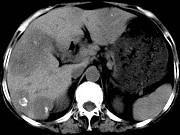

问题 女,55岁,腹胀,肛门闭气,消瘦乏力,肝区疼痛,CT检查如图,最可能的诊断为()

选项 A.多发性肝脓肿 B.肝癌肝内转移 C.肝淋巴管瘤 D.肝脏囊腺瘤 E.结肠癌肝转移

答案 E